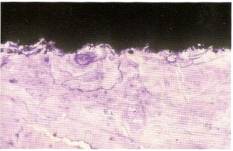

Рис.1. Начало процесса остеокондукции. Рис.1. Начало процесса остеокондукции.

На первом этапе остеокондукции фибрин проникает в очаг заживления и фиксируется к поверхности имплантата (Рис.1). Т.о способность поверхности имплантата сохранять фибриновые нити во время ретракции кровяного сгустка, определяет количество мигрирующих к леток, которые достигнут имплантат.

Первая и наиболее важная фаза остеоинтеграции – остеокондукция, которая заключается в привлечении и миграции остеобластов на поверхность имплантата, через остаток кровяного сгустка, сформированного вокруг имплантата. Отметим, что наиболее важные этапы внутрикостного заживления предшествуют костному образованию.